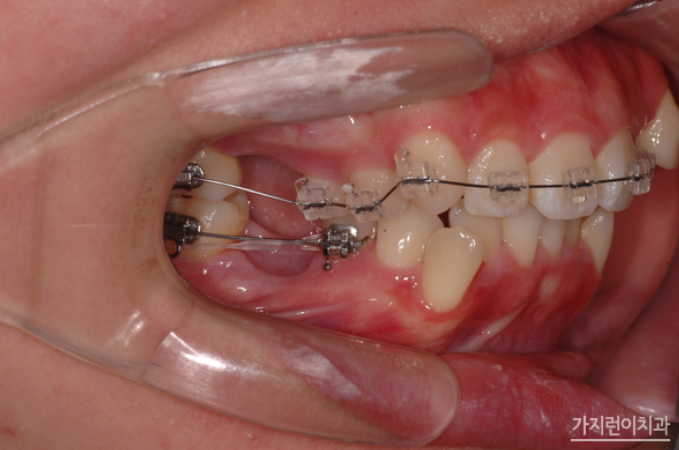

위 환자의 경우 상악 돌출입 증상과 더불어 심한 충치로 인해 발치가 불가피한 악조건을 갖고 있었는데요. 충치는 정도가 심하면 결국 발치를 하게 되고 인공치아를 식립해야 하는 과정을 밟게 되는데요. 그런데 환자의 경우 불규칙적인 치열의 재배열과 더불어 콤플렉스로 자리잡은 돌출입도 교정으로 진행해볼 수 있었습니다. Modified Bonded Cantilever Spring (MBC spring) 교정으로 사랑니에 직접 부착해 사랑니를 세우는 교정을 진행하게 되었는데요. 사랑니가 쓰러져 있는 상태라면 기존의 교정장치를 부착하기 어렵기 때문에 개발된 장치를 사용하고 있습니다. 그러면 장치를 착용한 후의 경과를 볼까요?

하지만 사랑니를 세우는 교정이라고 해서 모든 사람이 Modified Bonded Cantilever Spring (MBC spring) 교정을 사용하지는 않는데요. 환자분의 경우 하악 어금니 발치 공간을 메우는 과정에서 사랑니가 쓰러져 있긴 했지만 교정장치를 부착할 수 있는 상황이었기 때문에 추가적으로 Modified Bonded Cantilever Spring (MBC spring)을 사용하지는 않았습니다. 대신 돌출입 해결을 위해 상악을 후방으로 이동하기 위해 교정용 스크류를 이용해 진행하게 되었는데요. 총 2년 3개월의 치료기간이 소요된 환자분의 교정전후 사진을 확인해볼까요?